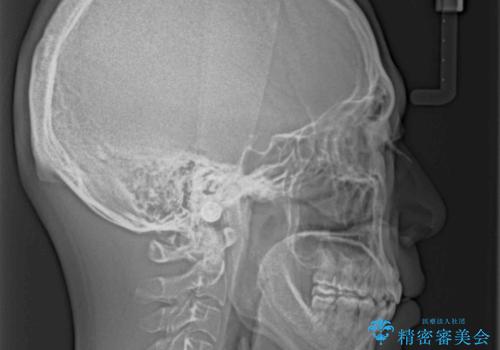

- 上下前歯の隙間と口元の出っ張った感じを気にして来院された患者様です。

上下の隙間は舌突出癖によるもので、またその癖により前歯が前方に出ている状態でした。

口元の出っ張りを改善するため、上下左右第一小臼歯4本を抜去し、ワイヤー装置にて矯正治療を行うこととしました。

舌の突出癖を改善するためのトレーニングを指導していましたが、なかなか改善することができず、ワイヤー装置を外してからも上下前歯に隙間ができやすい状況でした。